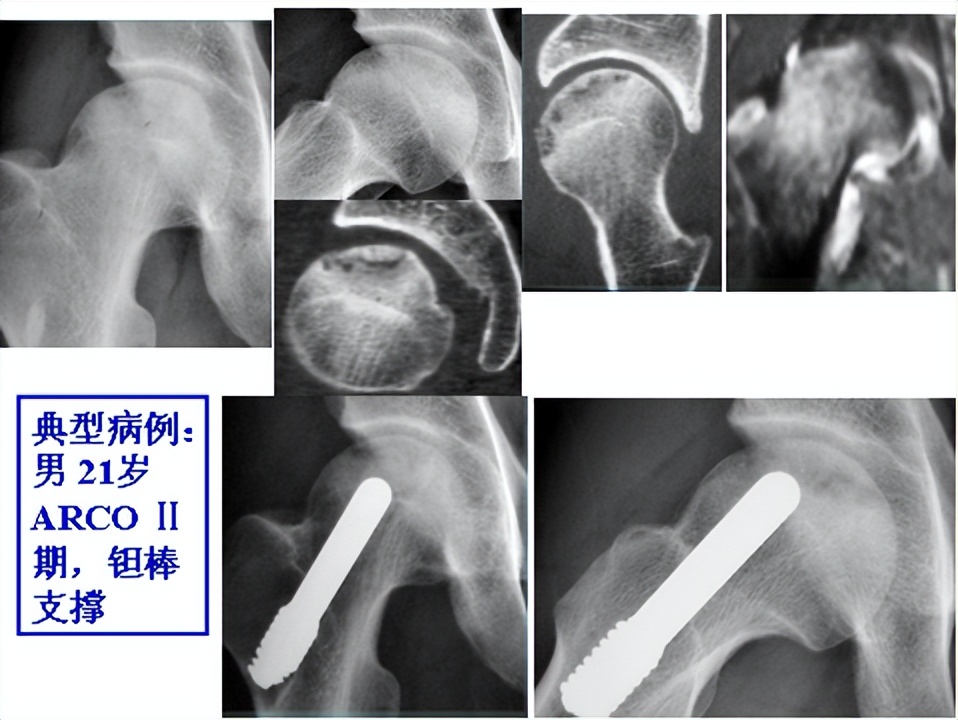

1.ARCO Ⅰ期~Ⅱ期:

本期特点:股骨头无塌陷,坏死偏于股骨头内侧,范围<1/3,无软骨下骨折。

手术方法2:钽棒支撑

2.ARCO Ⅱ期~ⅢA期: